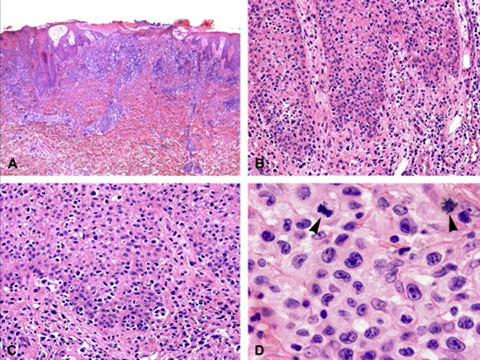

Cutaneous lymphoid hyperplasia in a 72-year-old man who presented with several purple-brown plaques on his cheeks and temples. A, The nodular infiltrate extends through the dermis with sparring of the overlying epidermis. B, It is characterized by scattered follicles with well-defined, reactive-appearing germinal centers, some of which have surrounding mantle zones. Many CD20-positive B cells are in the reactive follicles (C), and more numerous CD3-positive small T cells are present in the interfollicular areas (D). B-cell clonality studies (not shown) were negative for a clonal IGH or IGK gene rearrangement. [19]